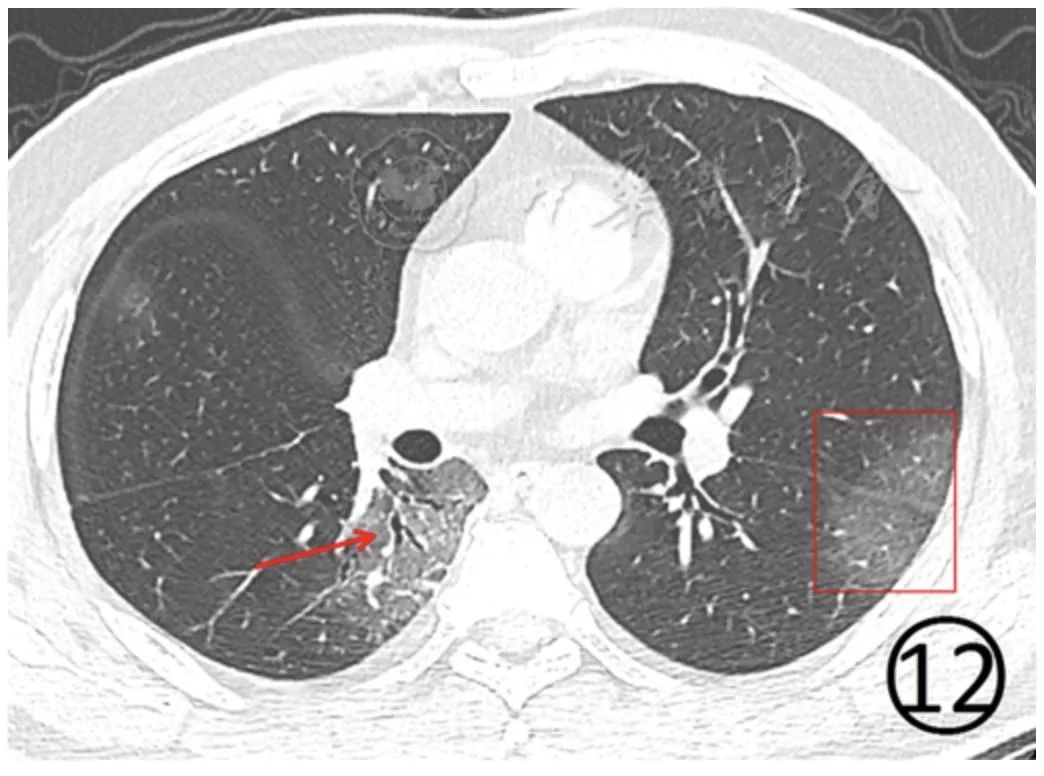

磨玻璃阴影内的细支气管管壁有增厚(图11),可见细支气管的充气支气管征(图11),血管影增粗,边缘欠光整,邻近的叶间胸膜有轻度增厚(图12)。

图12 男,55岁。CT平扫肺窗显示左肺上、下叶见磨玻璃阴影,左侧斜裂胸膜轻度增厚、模糊(红色框内)。右肺下叶背段之亚段性磨玻璃阴影内细支气管柱状增粗(↑),胸膜下局部实变并有小叶间隔增厚、移位。部分病变呈亚段性分布的大片磨玻璃阴影,病变内小血管增多,类似于细网格状阴影或"铺路石征" (图13,图14)。部分磨玻璃阴影有"反晕征" (图15)。